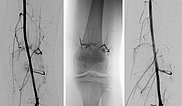

Schrittweise weitere Embolisation der hauptsächlichen Areale der arteriovenösen Malformation, hier am Knie. Der Ausguss (sogenannter Cast) durch das röntgendichte Embolisat (Ethylen-Vinyl-Alkohol-Kopolymer) zeigt den Verschluss bis in kleinste Gefäße.

In der DSA vor Embolisation (linkes Bild) finden sich kniegelenksnah multiple feine AVMs. Im Nativröntgenbild nach Embolisation ist das röntgendichte Embolisat zu sehen (mittleres Bild), das die arteriovenösen Fisteln ganz ausfüllt. In der DSA nach Embolisation (rechtes Bild) ist der gesamte Nidus der AVM verschlossen, keine sichtbaren arteriovenösen Fisteln mehr.